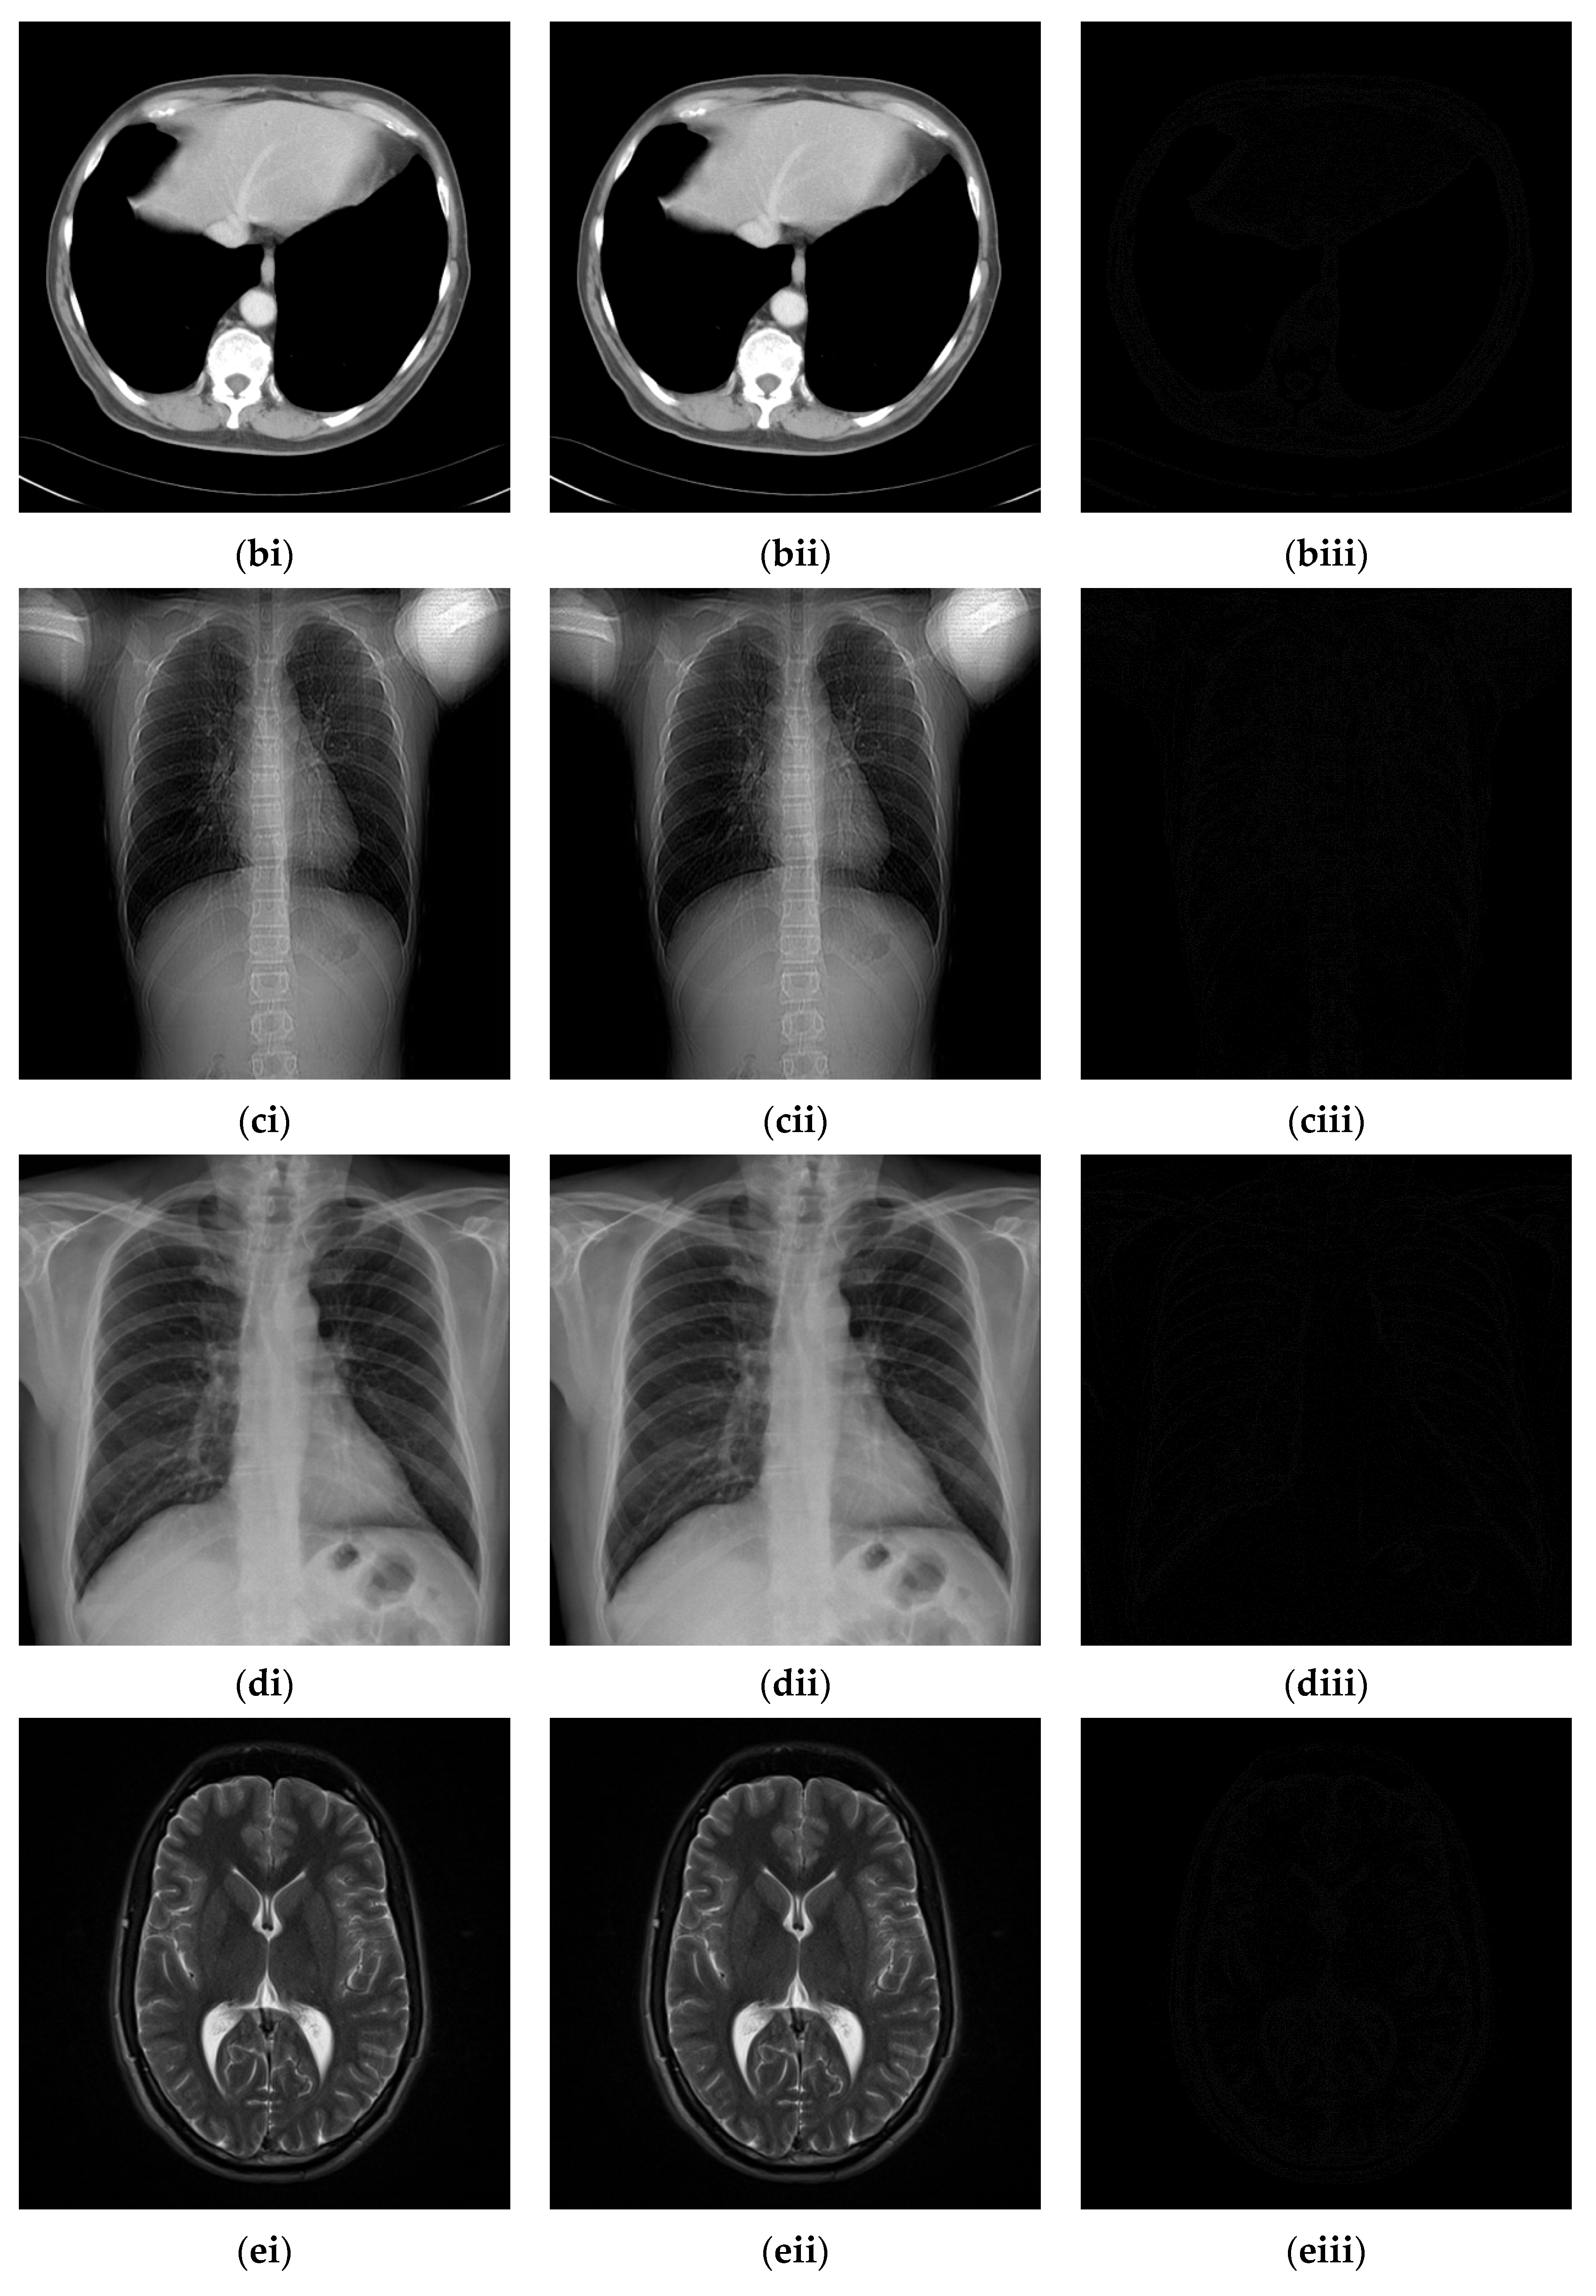

Figure 10.

Six medical test images; (a) Brain CT scan image (i); (b) Brain CT scan image (ii); (c) Thorax X-ray image (i); (d) Thorax X-ray image (ii); (e) Brain MRI scan image (i); (f) Brain MRI scan image (ii).

4.2. Experimental Results for Medical Images

Since the interpolation-based RDH schemes are designed for the special purpose of embedding patient information into medical images, the performance of our proposed adaptive RDH scheme on medical images is the main concern. Figure 11 shows the original image and its corresponding confidential image with 2 bpp secret data embedded, and images showing the difference between the original medical images and their confidential images. The difference images (aiii–fiii) in Figure 11 show almost nothing, which indicates that the proposed scheme does not look much different from the original image after hiding and will not draw the eavesdropper’s attention.

Figure 11.

The original images, the confidential images, and the different images; (ai–fi) The cover images; (aii–fii) The confidential images; (aiii–fiii) The difference between the cover images and the confidential images.